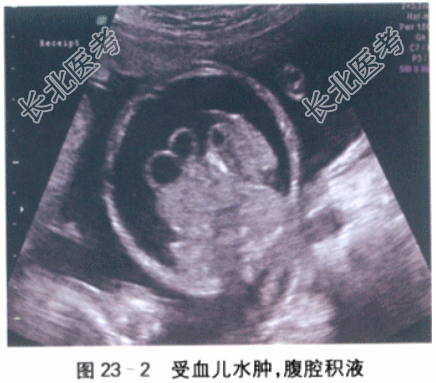

- [材料题] 患者,女性,32岁,已婚,因“G₂P₀,停经22周,腹胀一周”入院。初潮15岁,月经5天/30天,无痛经。末次月经2021-4-13。停经35天查尿HCG(+),孕产期2022-1-20。停经10周当地医院超声提示双胎妊娠。唐氏筛查未做。在当地医院每月做一次超声。于1月前(孕18周)在当地医院行超声检查未提示异常。近一周,自觉腹胀严重,平卧睡后有胸闷不适主诉。随即到当地妇幼保健院行超声检查:宫内两个胎儿,羊水多,羊水指数360mm。当地医院拟诊“孕22周,双胎妊娠,羊水过多”,建议转至上级医院诊治。既往体健,除人工流产外,无其他手术和外伤史,家族无遗传病及肿瘤病史,无双胎家族史。0-0-1-0,3年前自然流产一次。体格检查:Wt72kg,Ht159cm,BP130mmHg/80mmHg,HR100次/min,一般情况良好,内科检查无异常,全身浅表淋巴结未及肿大,腹隆,无压痛,下肢水肿(++)。腹部张力高,可见腹壁浅静脉怒张。产科检查:腹围122cm,宫高35cm,胎心140/152次/min,胎位不清。骨盆外测量无异常。实验室和影像学检查:血常规检查:Hb107g/L,RBC4.2×10¹²/L,WBC3.7×10⁹/L,N71%,PLT121×10⁹/L。凝血功能检查:APTT32s,PT12s。肝肾功能检查:AST23μmol/L,ALT35μmol/L,TP60g/L,Alb31g/L,TB10μmol/L,BUN5.6mmol/L,Cr90μmol/L。肝炎指标及HIV,RPR:均阴性。超声检查:2021-7-8外院B超图片提示一个孕囊,两个胚芽。入院后B超检查:胎盘后壁。宫内可见两个胎儿,大胎儿体重位于该孕周第52百分位,羊水深度18.3cm,心胸比增大(59%),静脉导管血流A波反流(见图23-1),脐血流舒张期倒置,大胎儿出现水肿和腹腔积液(见图23-2)。小胎儿体重位于该孕周第9百分位,羊水过少(深度0.9cm),呈包裹趋势,膀胱消失(见图23-3)。脐血流、大脑中动脉血流、静脉导管多普勒血流无异常。两胎儿体重相差26%。宫颈长度37mm。